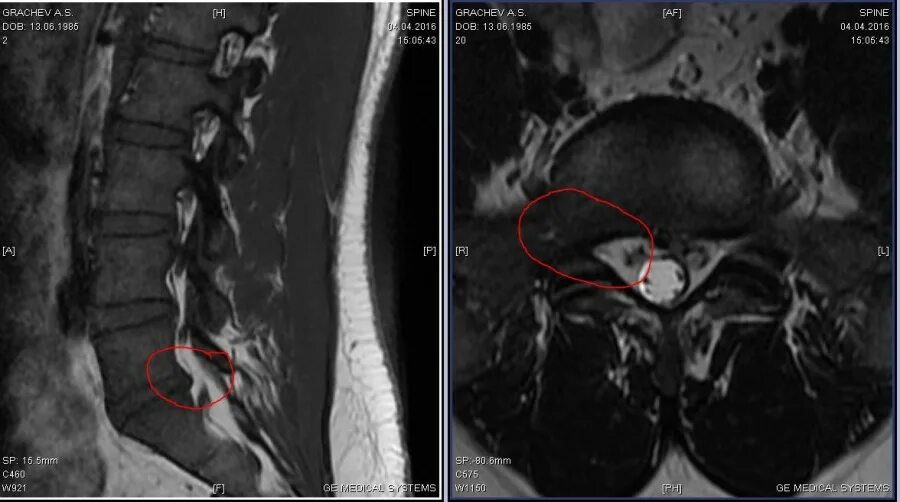

Грыжа диска мрт